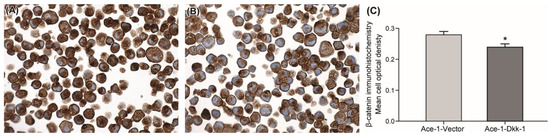

3.2. Immunohistochemistry

3.3. AP-1 Reporter Activity